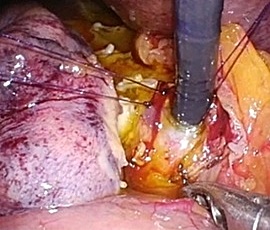

手術画像(腹腔鏡)